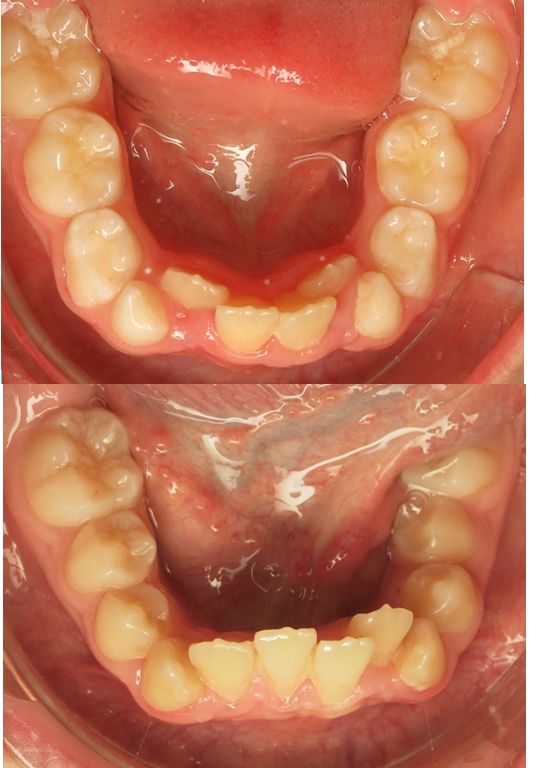

◼“ Sa mâchoire inférieure est trop petite, regardez-moi ça! il se mord le palais!” Vous ouvrez magistralement votre tiroir et vous sortez une boiîte jaune marquée :denture mixte Vous en…

Tous les parents, tout le corps médical se posent cette question On entend tout et son contraire! ◼ “ Mais docteur, mon fils n’a pas ses dents définitives, pourquoi…

On a est parfois un peu leste niveau davier. Devant un gosse de 7-8 ans qui a un encombrement incisif, ne vous arrive-t-il pas de sortir le davier pour “faire de la…